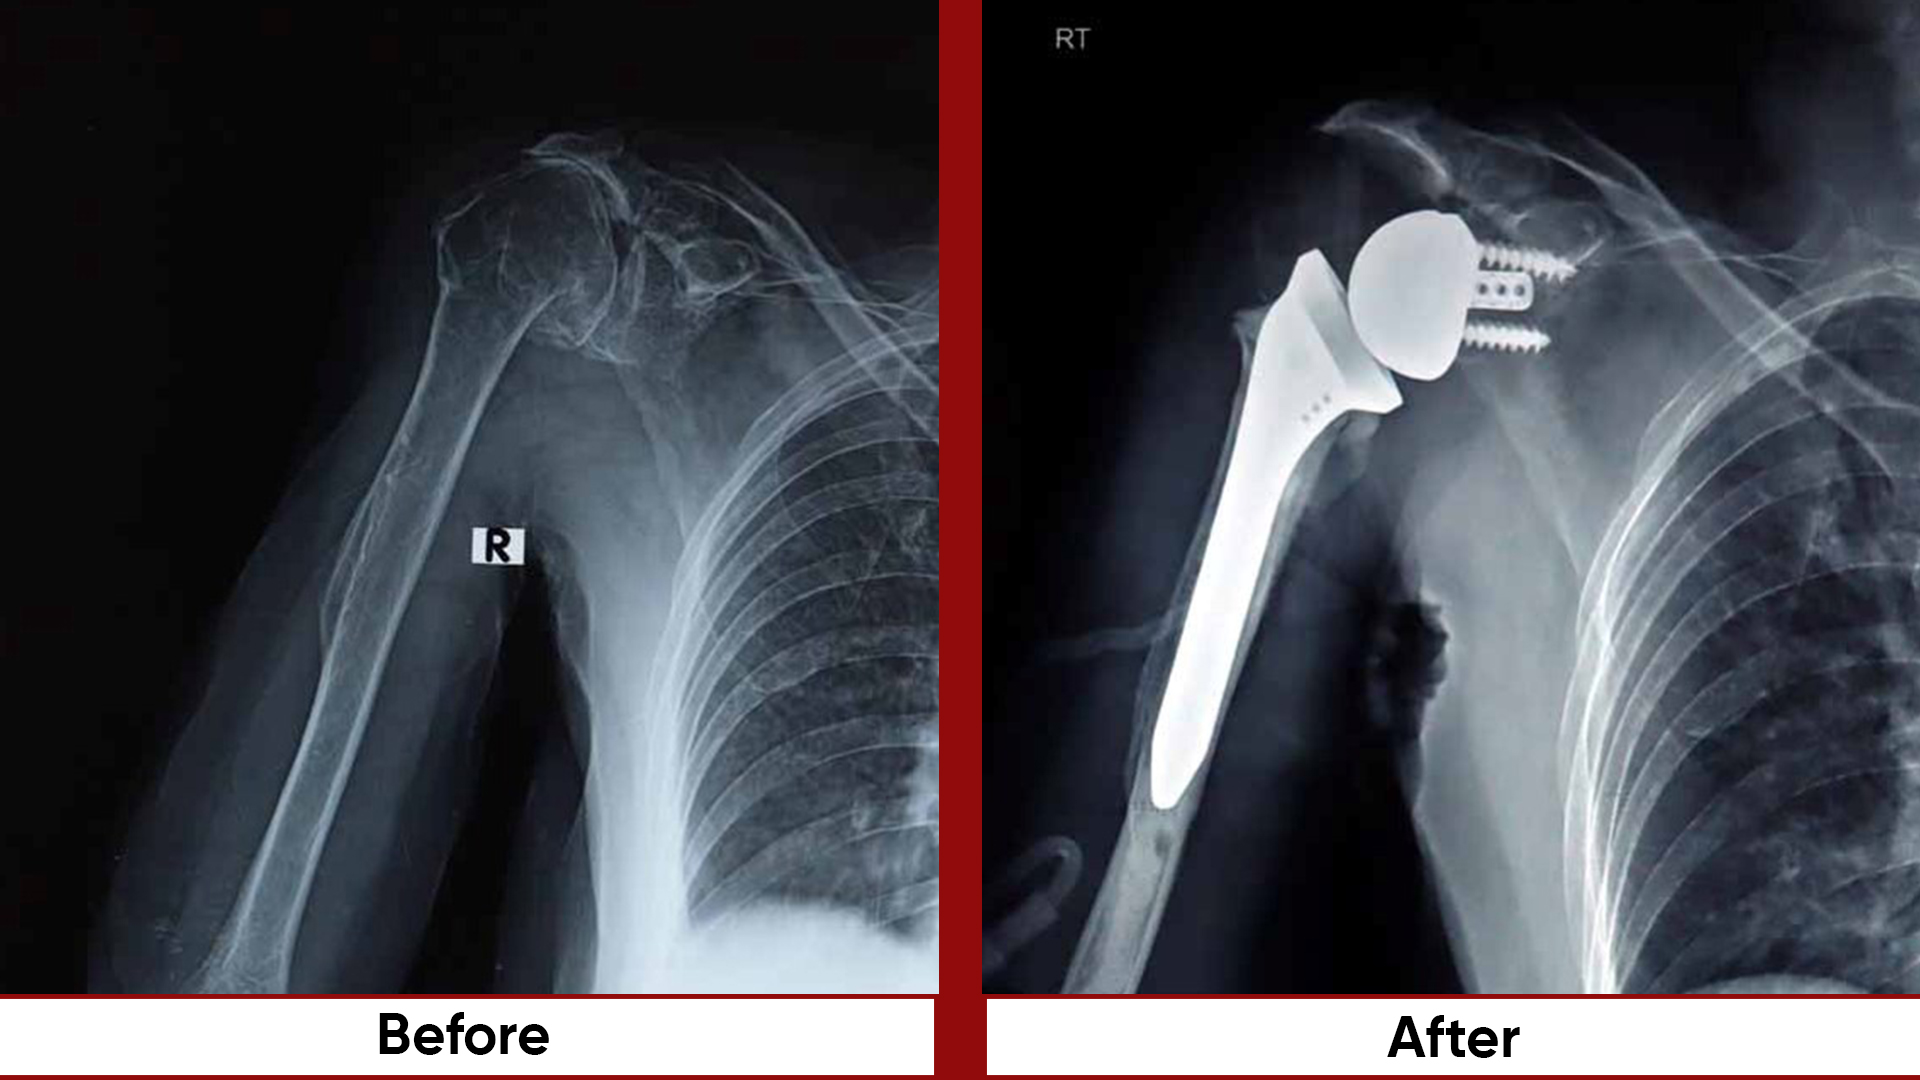

• Arthroscopic Surgeries (Knee & Shoulder)

• Arthroplasty

•  Arthroscopy / sports injuries.   Busiest unit